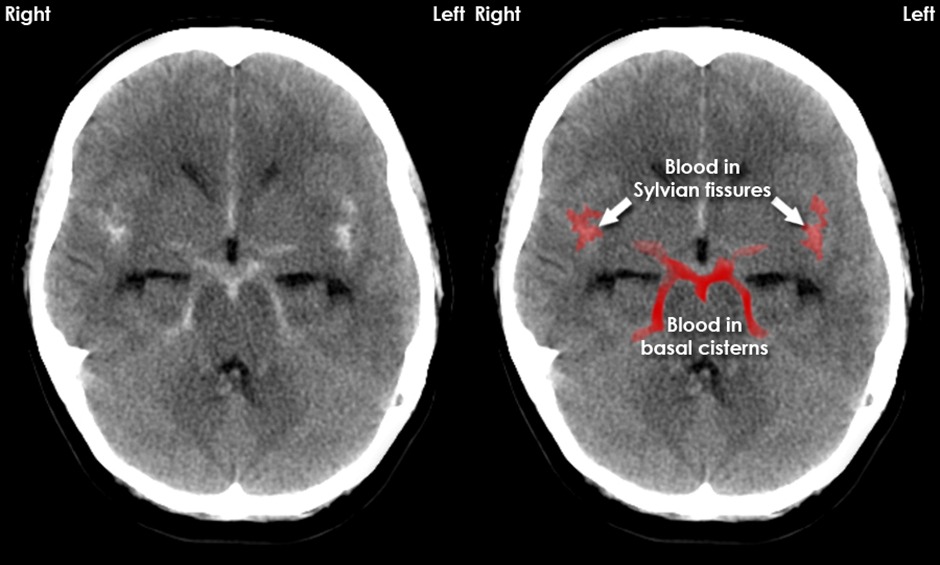

- CT head without contrast (hyperdensities in the suprasellar cisterns extending peripherally)

- When CT head without contrast is normal and there is still high suspicion for SAH (over 6 hours from onset of symptoms, lumbar puncture (LP_ is indicated